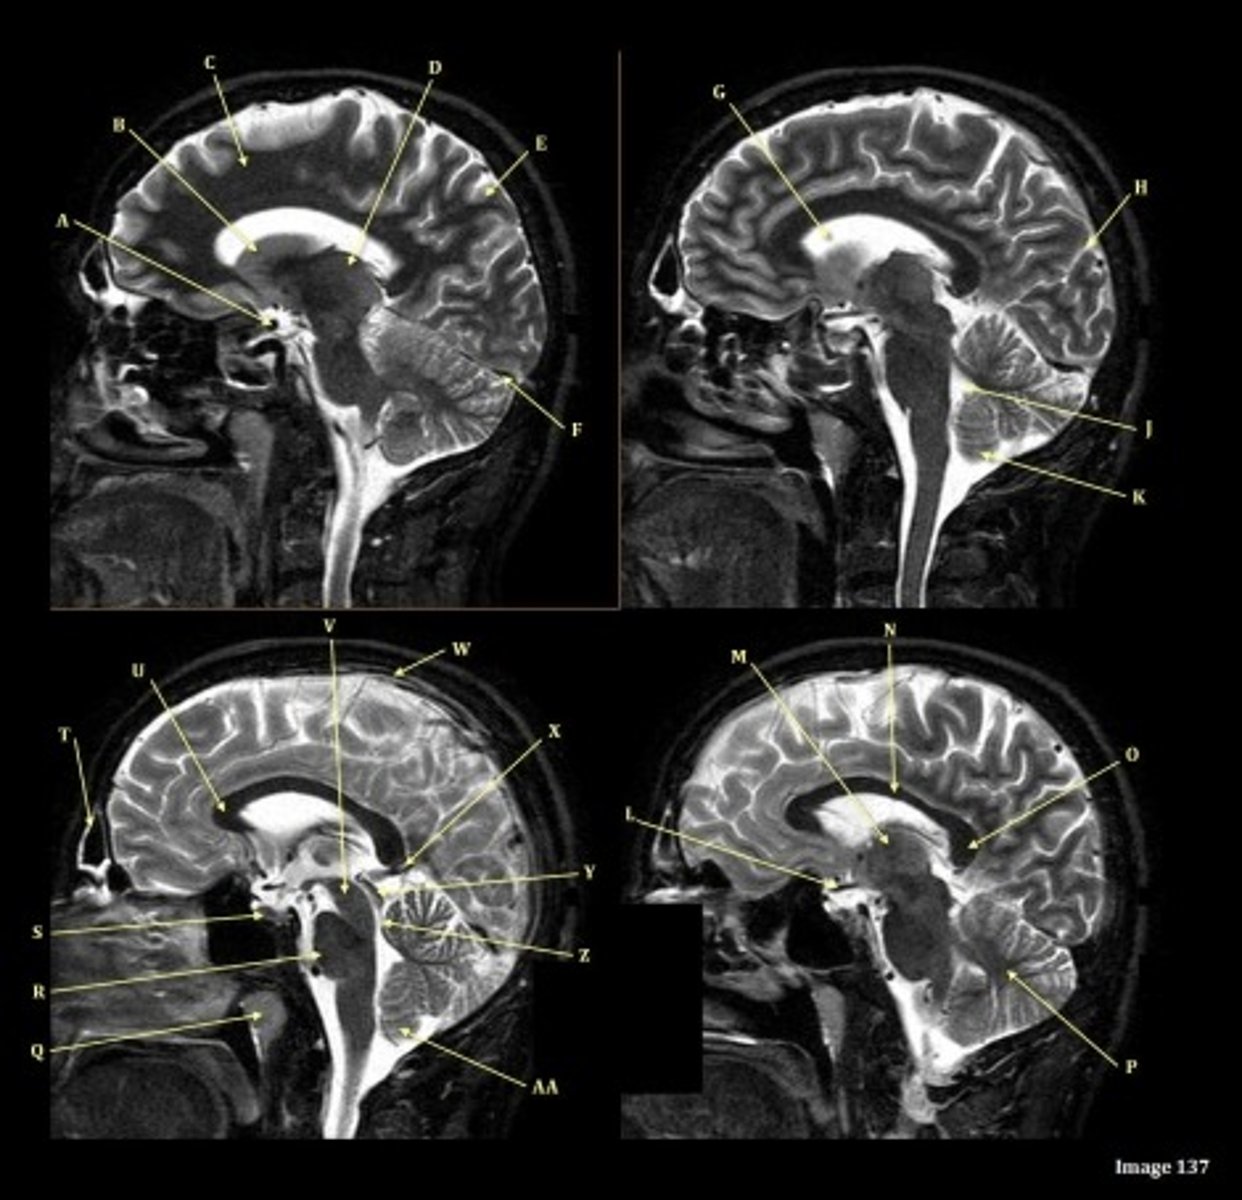

What type of sequence?

T2 FLAIR; Sagittal

A FLAIR (Fluid Attenuated Inversion Recovery) sequence is utilized to suppress signal from cerebrospinal fluid (CSF).

A

lateral ventricle

B

corpus callosum

C

thalamus

D- separates what

tentorium cerebelli- cerebrum (occipital and temporal lobes) from brainstem and cerebellum

E

fourth ventricle

F

medulla oblongata

Letter N in Image 137 is pointing to what type of tissue?

White matter

The corpus callosum is the only white matter tissue structure found in the midline sagittal slice of the brain.